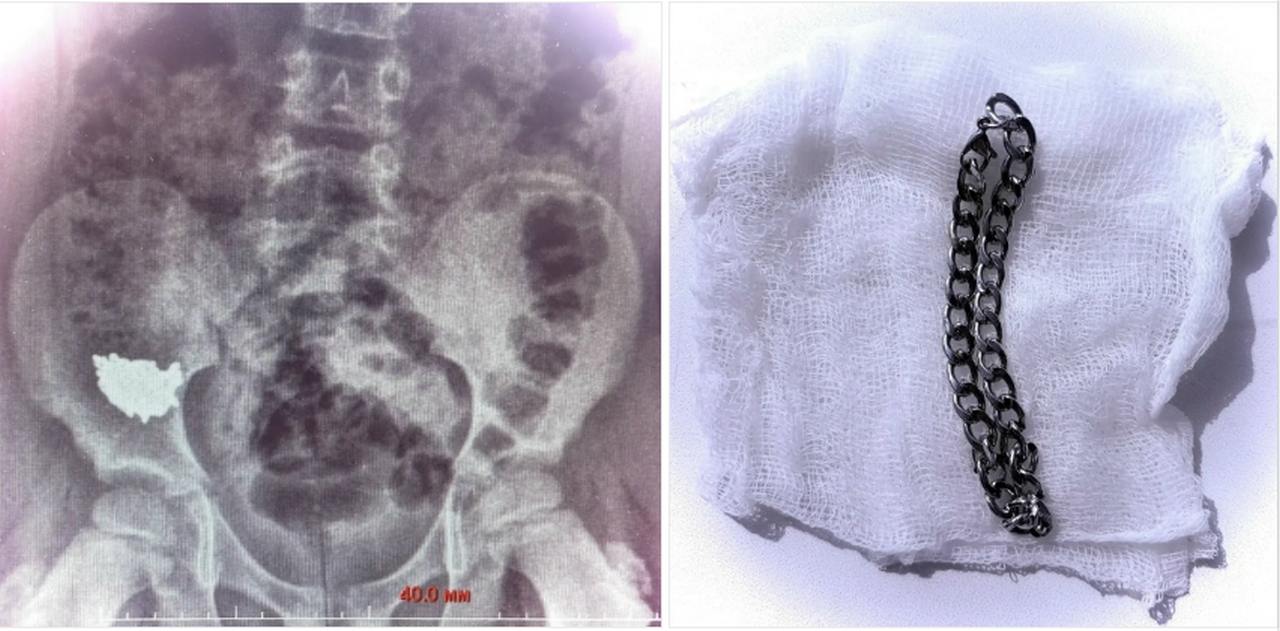

Рентгеновский снимок показал, что инородное тело находилось в правой подвздошной области живота. Ребёнок был госпитализирован для наблюдения. Поскольку снимки на третьи и четвёртые сутки не показали перемещения цепочки по желудочно-кишечному тракту, врачи приняли решение о срочном хирургическом вмешательстве из-за высокого риска перфорации кишки и развития перитонита.

В ходе операции, проведённой под общим наркозом, врачи сначала выполнили колоноскопию, но цепочка обнаружена не была. Затем, проведя ревизию брюшной полости, медики обнаружили инородное тело и извлекли его через просвет аппендикса, завершив операцию аппендэктомией.